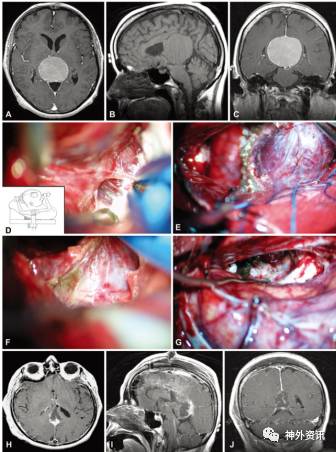

图6. 1例患者术前术后MR影像及术中照片。术前MRI(A.轴位;B.矢状位;C.冠状位)提示肿瘤起源于镰幕交界区,位于大脑内静脉上方,将胼胝体压部推向前下方,呈均匀强化。D.术中在胼胝体压部上方显微分离;E.显露肿瘤;F.瘤内减压并沿肿瘤包膜分离后;G.切除肿瘤。术后MRI(H.轴位;I.矢状位;J.冠状位)提示肿瘤全切除。